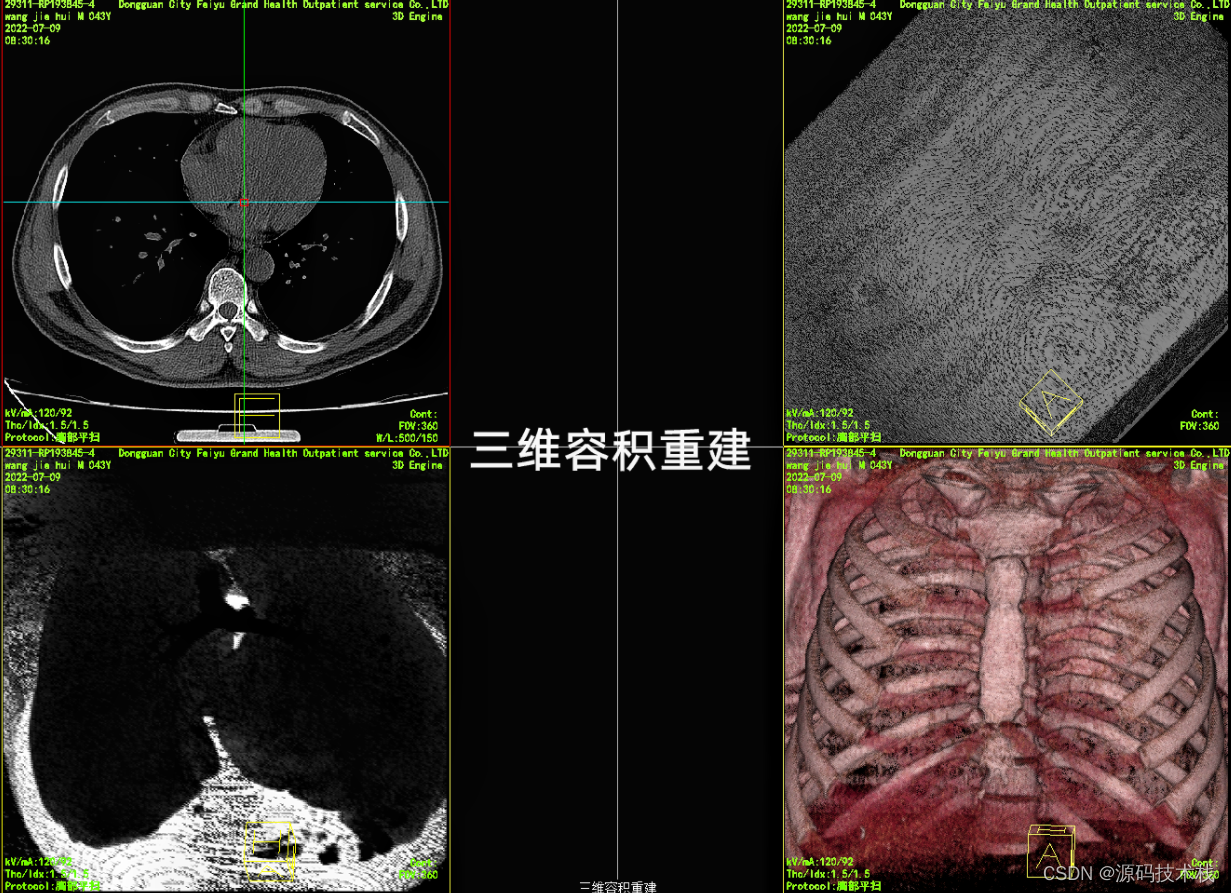

是基于平扫和各种冠状位、矢状位及水平位的数据,用后期电脑重新合成的数据。将获取的冠状位、矢状位和水平位的数据整合后还原出器官三维立体的形象,可以直观地看到何处有病变,而且根据血流的多少添加色彩,看起来就更加直观。

下面就是三维重建的图像:

3.VRT(容积成像)

不需要重建物体的表面几何信息,通过计算体素的阻光度、颜色、梯度等,然后直接把三维灰度数据投影到二维屏幕上,在投影时累计半透明体素对光线的透射吸收作用。它是目前的常用方法。它保持原图像所有信息,同时显示空间结构和密度信息。